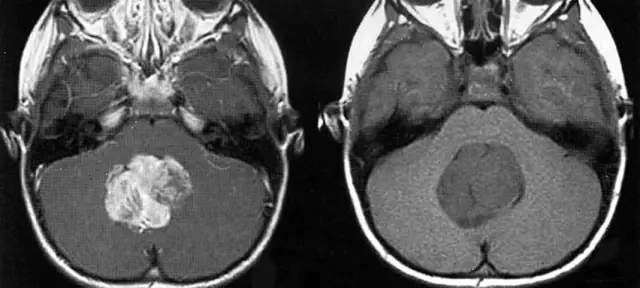

Теперь шведские исследователи Леннарт Харделл, Майкл Карлберг и Кьелл Ханссон Милд из Института онкологии при университетской больнице города Эребру опубликовали в специализированном журнале «Журнал патофизиологии» исследование, посвященное вывод о том, что с использованием мобильного телефона также связан повышенный риск возникновения так называемых глиом (злокачественных опухолей головного мозга). Аналогичным образом это относится и к беспроводным телефонам. Ученые винят в этом «высокочастотное электромагнитное излучение приборов». Дети и молодые люди особенно подвержены риску.

В рамках своего исследования ученые проанализировали возможную связь между использованием сотового или беспроводного телефона и возникновением злокачественных опухолей головного мозга. Они оценили данные 1498 пациентов с опухолью головного мозга и 3530 здоровых добровольцев из двух предыдущих исследований, чтобы определить влияние излучения мобильных телефонов на риск развития опухоли головного мозга. Шведские исследователи пришли к выводу, что как использование мобильных телефонов, так и использование беспроводных телефонов связаны с повышенным риском развития глиомы. Каждый год использования приводит к дальнейшему увеличению риска заболевания. Исследователи сообщают, что любой, кто пользуется сотовым телефоном более 25 лет, подвергается в три раза большему риску, чем средний. По словам Харделла, Карлберга и Ханссона, после 15-20 лет использования риск по-прежнему примерно в два раза выше, чем в среднем по популяции.

Не только продолжительность использования сотового телефона, но и возраст, в котором он впервые им воспользовался, оказали влияние на риск возникновения опухолей головного мозга, считают ученые. Испытуемые, которые уже звонили по беспроводным и мобильным телефонам в молодом возрасте, подвергались особому риску. Риск заболевания был значительно выше при первом использовании устройств в возрасте до 20 лет, чем при их использовании позже. По словам исследователей, дети, в частности, не должны пользоваться мобильными или беспроводными телефонами, так как излучение проникает в их череп намного глубже, чем у взрослых. Кроме того, их мозг все еще развивается и поэтому особенно уязвим для вредных воздействий.